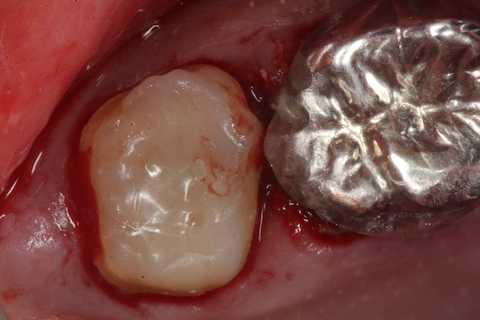

40代男性、左上7、歯根破折

今日は再建した歯を抜歯窩に挿入して固定するまで。

スーパーボンドとCRによる歯牙固定が良いと思う。

隣接歯の接着面には接着性を良くするためにグルーブを形成し、あらかじめスーパーボンドを流しておく。